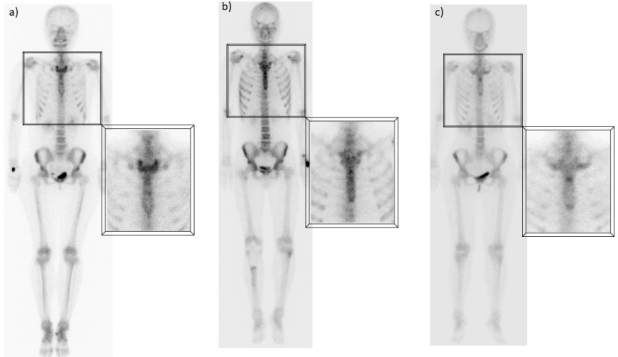

E) Captación esternal

Generalmente este hallazgo se atribuye a cambios degenerativos de las articulaciones esternoclaviculares, bastante frecuentes y que aumentan con la edad, ya que se trata de articulaciones sinoviales que soportan un estrés constante(10). Sin embargo, algunos estudios han descrito patrones de captación normales específicos en el esternón, relacionados con la edad, que no necesariamente representan cambios articulares. Los hallazgos sugieren que una captación difusa, homogénea y leve es normal en pacientes jóvenes, mientras que un patrón más heterogéneo y segmentario, con mayor actividad en los bordes óseos, también puede ser completamente normal en pacientes de edad avanzada(11). Asimismo, la captación focal a nivel de la articulación manubrio-esternal o ángulo de Louis es un hallazgo frecuente, independientemente de la edad, que en la mayoría de los casos puede explicarse por la osificación a nivel de la sínfisis o la presencia de crestas óseas (fig. 5).